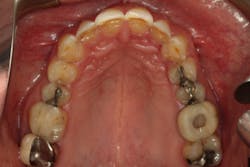

One of our goals was to avoid preparing the mandibular anterior teeth and still achieve proper anterior guidance. Fortunately, the orthodontics combined with direct bonding provided a more-than-adequate result, so we were able to forego any restoration on the mandibular arch at this time. Again, our goal is always to do the least amount of dentistry to obtain the best possible results. Sometimes, providing comprehensive dentistry still involves a significant amount of treatment, but it’s important to challenge ourselves to remain conservative and preserve as much tooth structure as possible.

Through working with Darren, we were able to provide the necessary treatment to obtain the five requirements of occlusal stability. He now has stable stops on all teeth, anterior guidance in harmony with the envelope of function, anterior teeth that provide immediate posterior disclusion in protrusive, and he no longer has working and balancing side excursive interferences.

Overall, the case closely followed our treatment plan blueprint because of proper diagnosis and planning. Darren was comfortable with his envelope of function, occlusal stability was restored, and he was thrilled with his natural, esthetically pleasing smile.